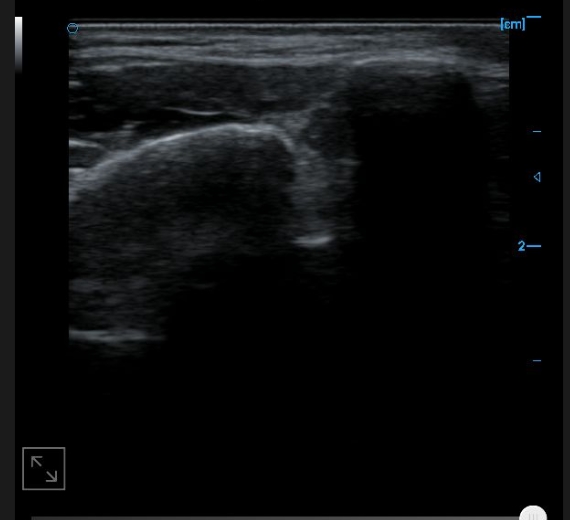

Patellar tendon B image

B-image of quadriceps tendon

Knee collateral ligament B image

B-image of femoral trochlear cartilage